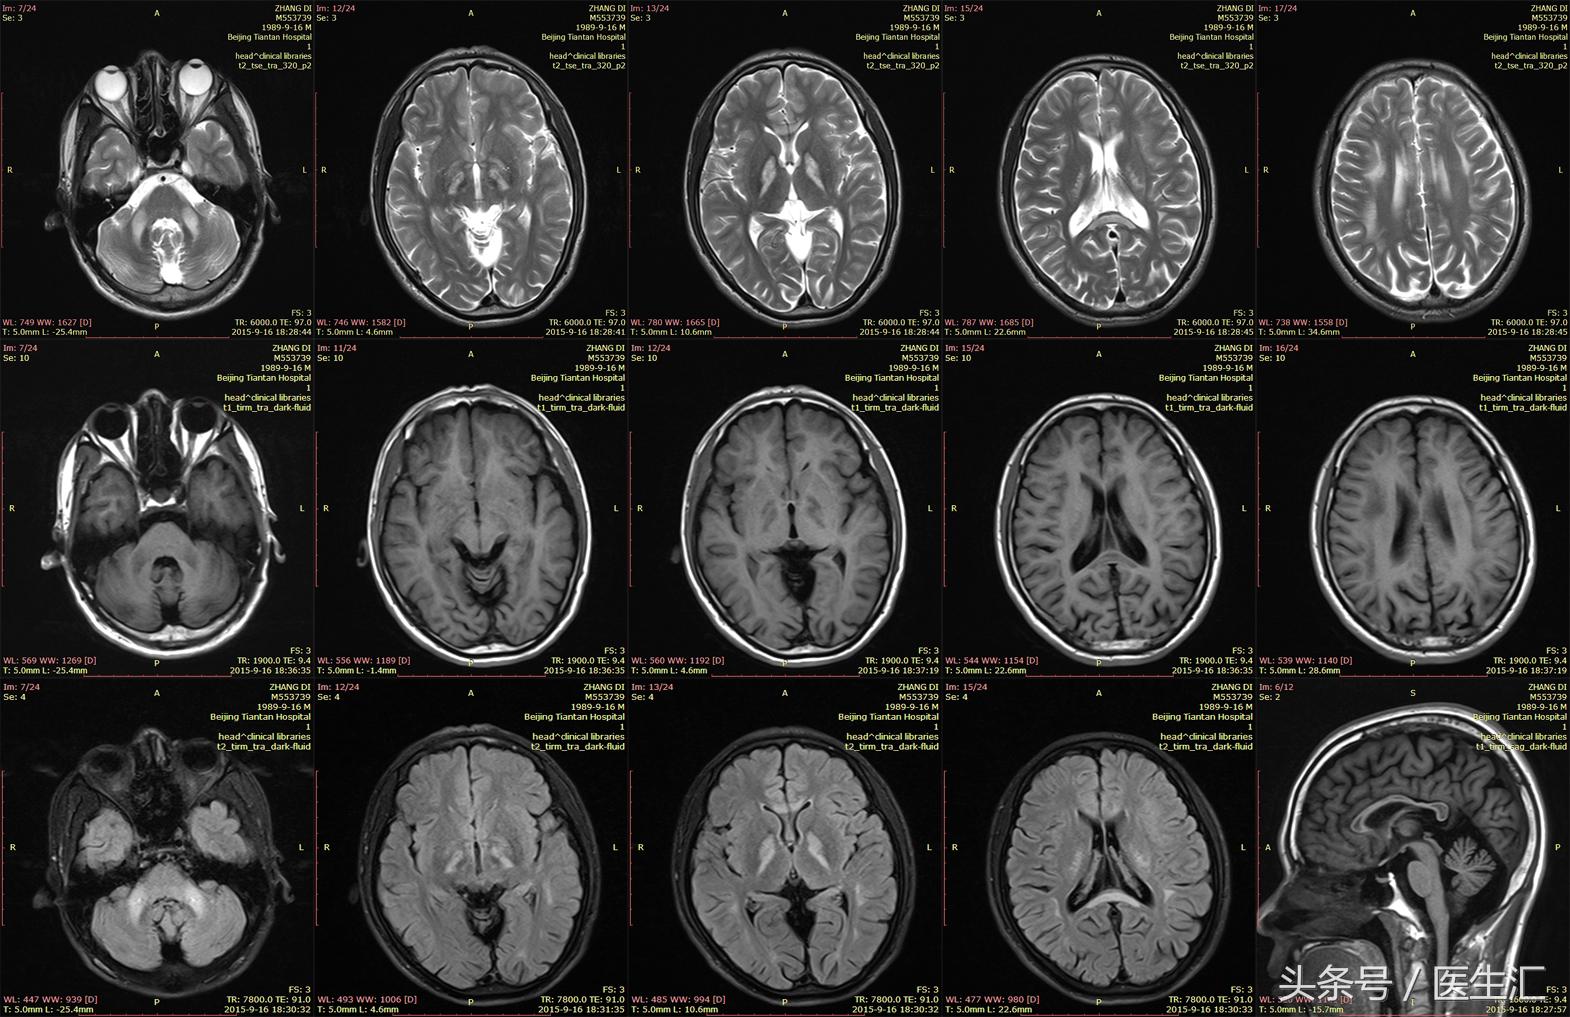

头颅MRI:(见图1)

专家判读:双侧弥漫脑白质病变